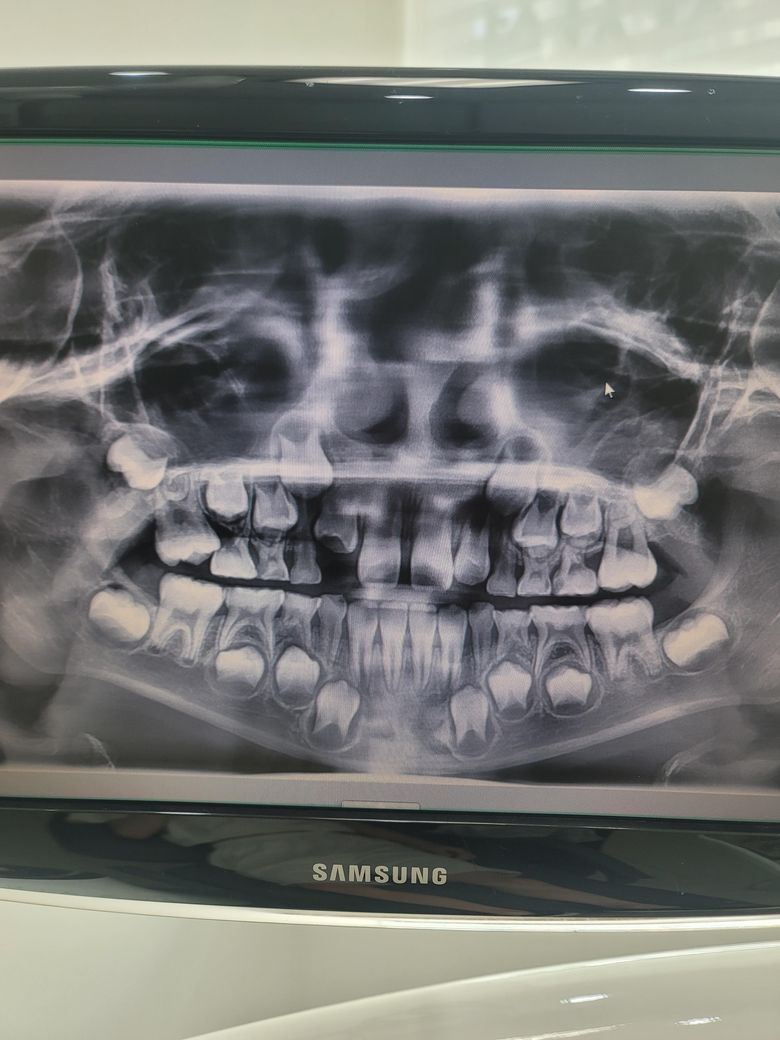

아이 치과엑스레이 사진 봐주세요.교정

초3아이예요

충치치료차 치과 방문했는데

교정이 필요하다고 교정치과에

가서 진료를 받아보라고 권유해

주셨어요. 설명해주시긴 했는데

좀더 자세한 치료방법과 치료시기

기간.비용등이 궁금합니다.

위쪽 유치들이 너무 빠른시기에 문제가 생겨서 영구치 맹출에 안좋게 작용이 될꺼 같아서 아마 영구치가 나올떄까지 공간을 유지하는 교정을 하자고 하신거 같습니다.

교정 치료의 경우에는 악골 성장이 잘 되지 않아 치아가 악골에 배열이 잘 되지 않게 되어 어긋날 때 하게 됩니다. 현재 상태에서는 크게 문제가 될 사항이 보이지 않으나 골격적으로 부정규합의 가능성이 있다면 교정치료를 해야할 수도 있습니다.

자세한 확인을 위해서 교정 치과에서 진료를 받아보는 것을 권유드립니다.

2. 일반적으로 성장기 교정의 경우 위, 아래턱 성장량을 조절하는 방식이 있을 수 있고 2~3년 소요됩니다

3. 비용은 치과마다 다릅니다.